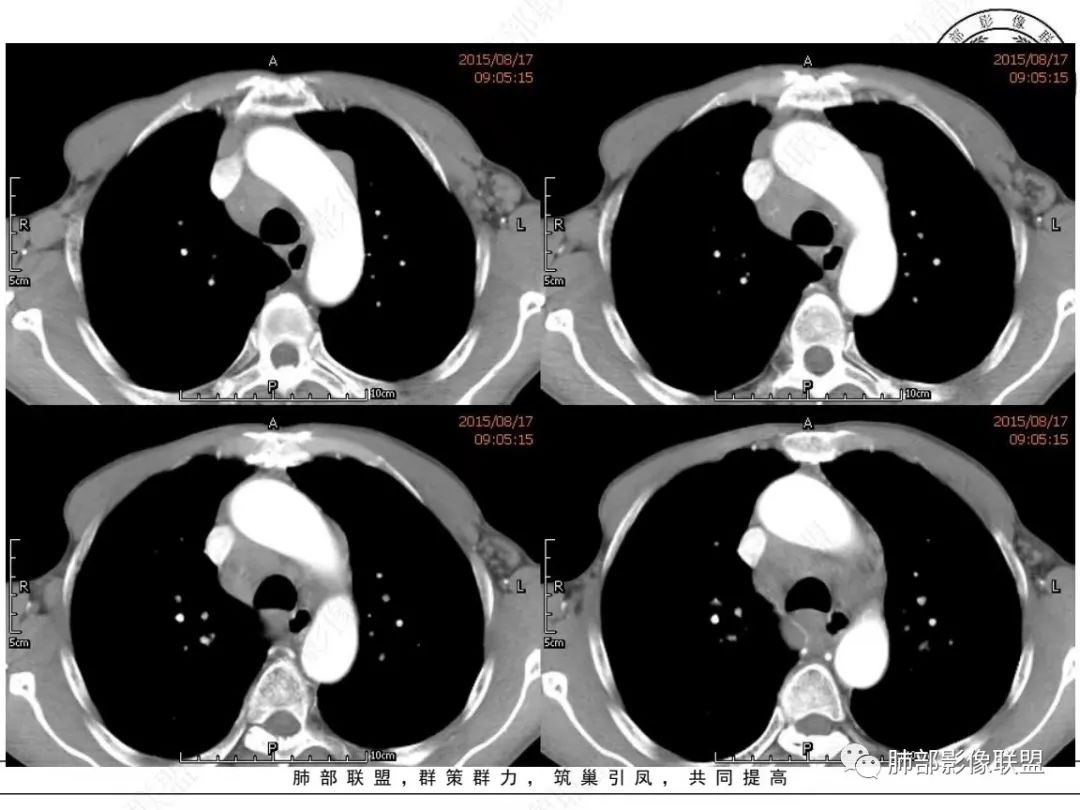

放射小白:老年男性,右侧肺门可见团块状占位包绕气管,气管受压变窄,纵隔见巨大团块状占位,另纵隔可见肿大淋巴结,增强肺门及纵隔肿块强化不明显,内部可见血管影,周围结构只是受压移位,另颌下淋巴结穿刺慢性淋巴结炎,首先考虑小细胞癌,鉴别淋巴瘤、结节病。

宇宙:右肺下叶小结节,右肺门及中后纵膈淋巴结肿大融合,强化均匀,主支气管、中间段及下叶支气管受压变窄,右下肺静脉受压变窄,考虑小细胞癌,鉴别淋巴瘤

丽:老年男性,纵隔及肺门多发肿大淋巴结,相互融合呈团块状,包绕支气管官腔,呈针尖样狭窄,增强后轻度强化,考虑小细胞肺癌

放射线:纵隔及肺门淋巴结肿大相互融合呈冰冻纵膈,支气管受压变窄呈针孔样,老年男性吸烟患者,考虑小细胞肺癌。

采莲:老年男性,有吸烟史,双颈部肿块,双肺纵隔淋巴结多发淋巴结肿大并融合成块,气管及右肺下叶支气管受压狭窄,考虑恶性,淋巴瘤可能,鉴别小细胞肺癌。

崔少钢:老年男性,有吸烟史,右肺下叶背段示小结节,纵隔、腋窝及右肺门淋巴结节肿大,气管受压狭窄,后纵隔软组织内示血管走行,考虑小细胞>淋巴瘤。

我只是邓较瘦:晨读老年男性,长期吸烟。右肺门、纵隔多发肿大淋巴结、融合成团块,中间支气管、右肺下叶支气管受压变窄,增强扫描强化程度较轻,血管包埋。另两侧腋窝亦见多发肿大淋巴结。常规恶性没问题,小细胞?淋巴瘤?但是於老师的病例总感觉没那么简单。

谢加平:纵隔内中后纵隔及右肺门淋巴结肿大,形成大肿块,整体密度均匀,并轻度强化,见“血管飘浮”征,包绕气管分叉及右主支气管及中间段支气管明显受压狭窄,并包埋右肺门血管束,无侵蚀破坏,右肺动脉后壁见压迹影,右肺下叶背段有阻塞性炎症,首选淋巴瘤,支气管超声内镜活检,明确诊断!